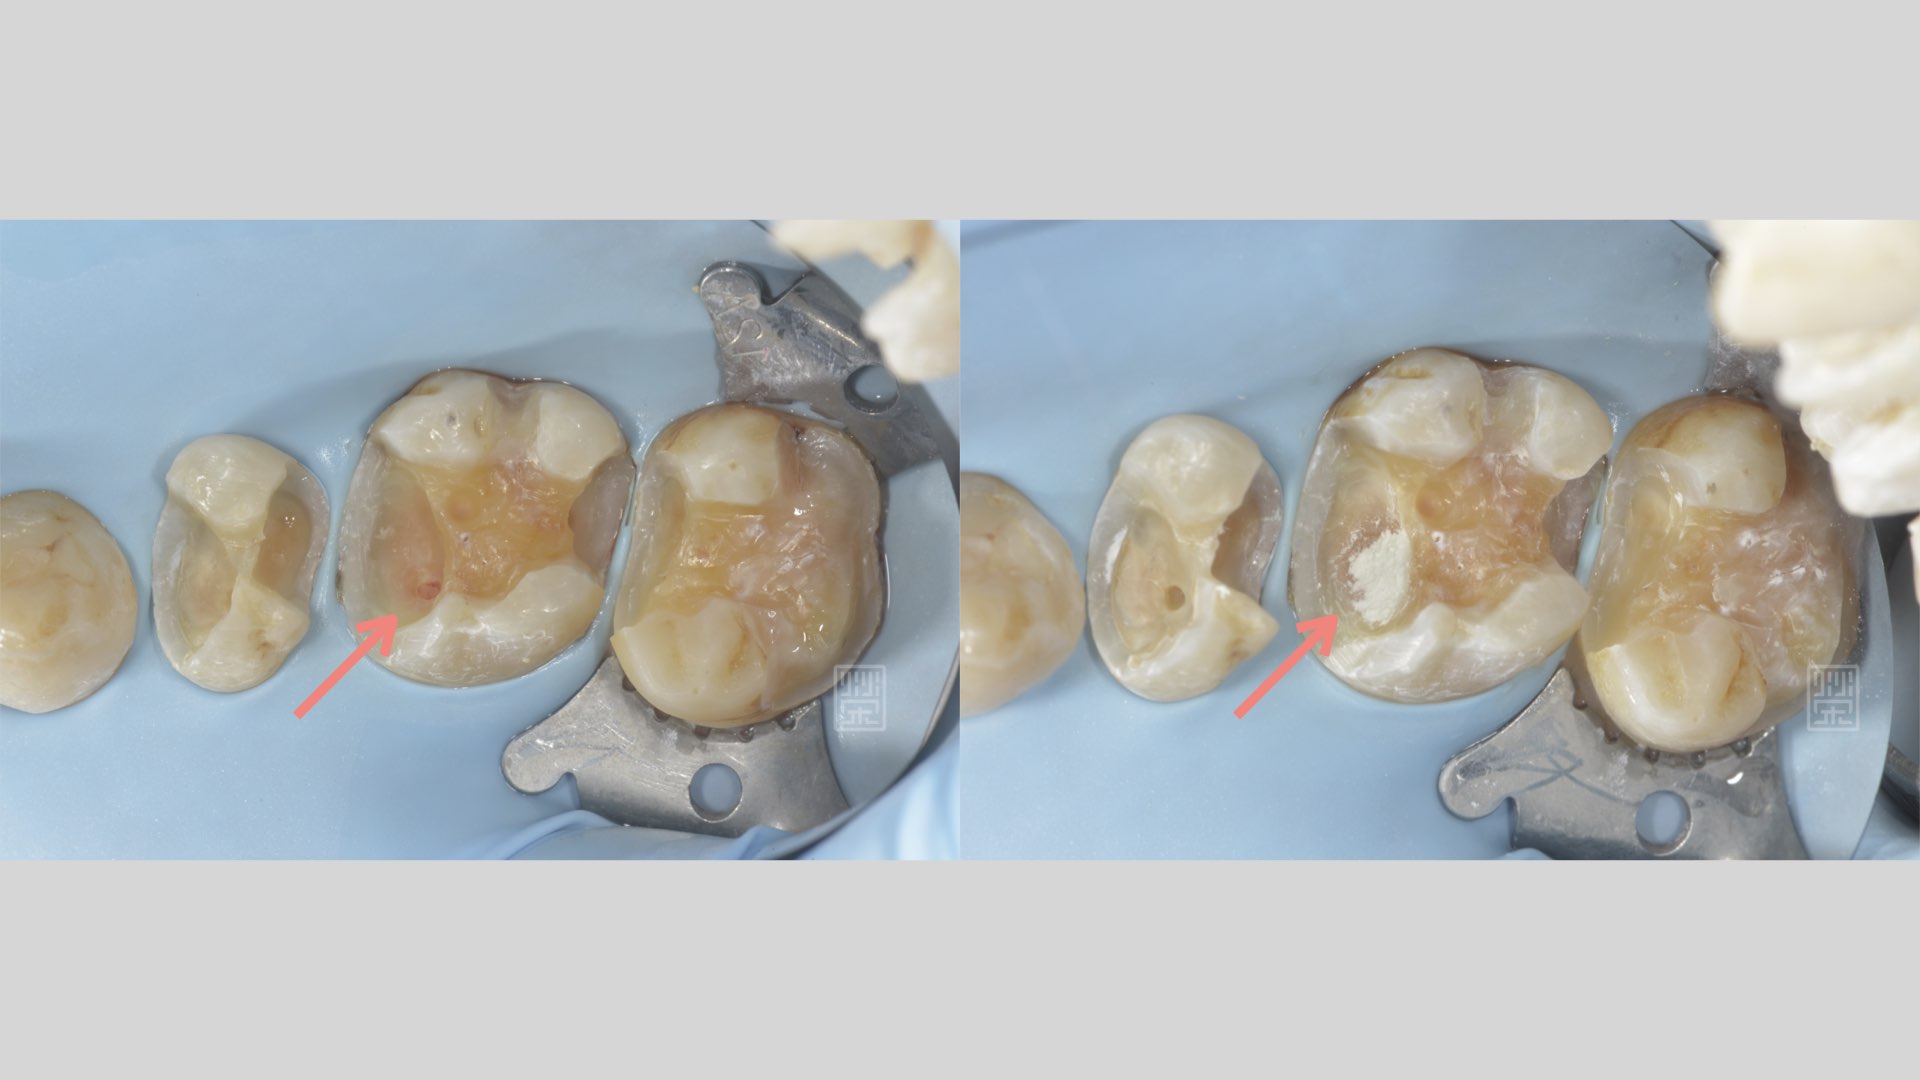

後牙蛀牙清除

後牙蛀牙清除後,牙髓受感染,MTA覆髓治療